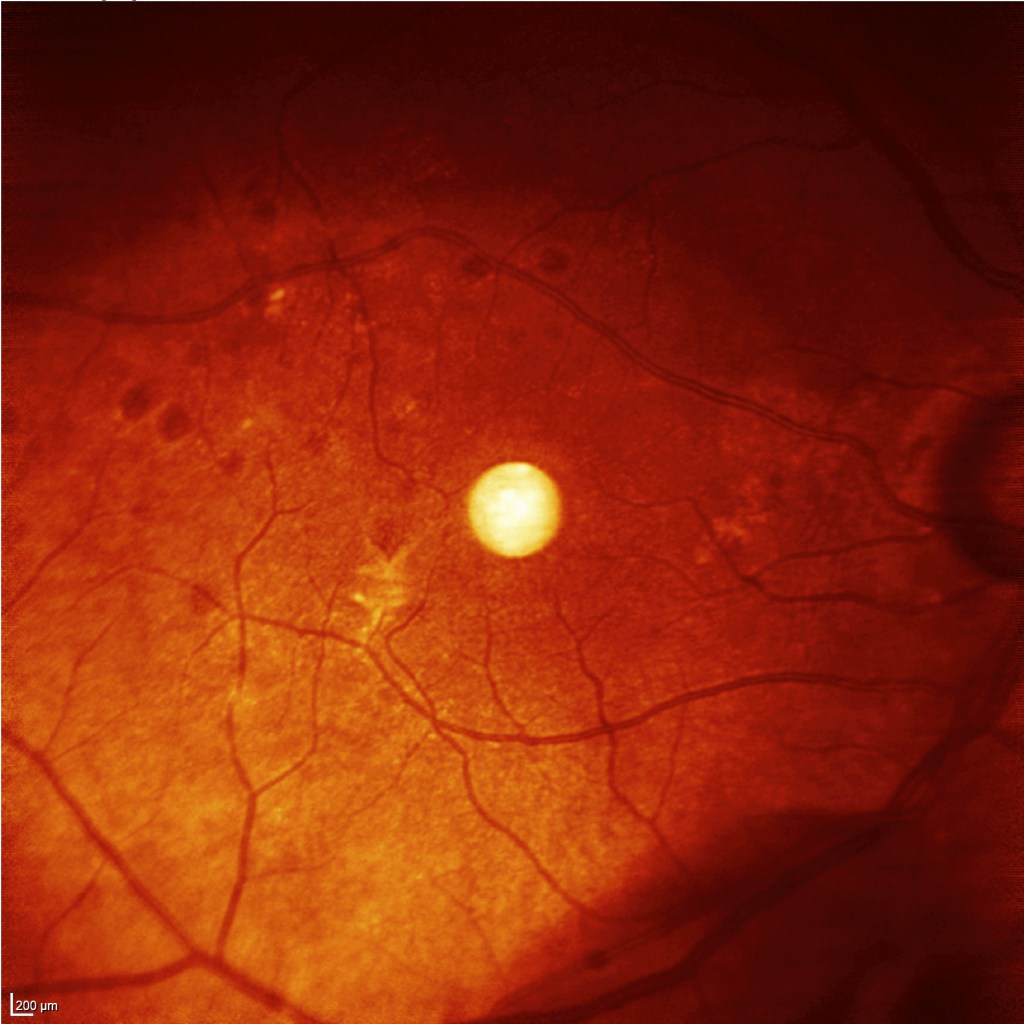

Observamos las retinografías previas y en hipotonía, donde se aprecian pliegues maculares:

Las OCTs previas y en hipotonía, con un registro claro de los pliegues maculares, con la consiguiente pérdida de calidad en la visión: